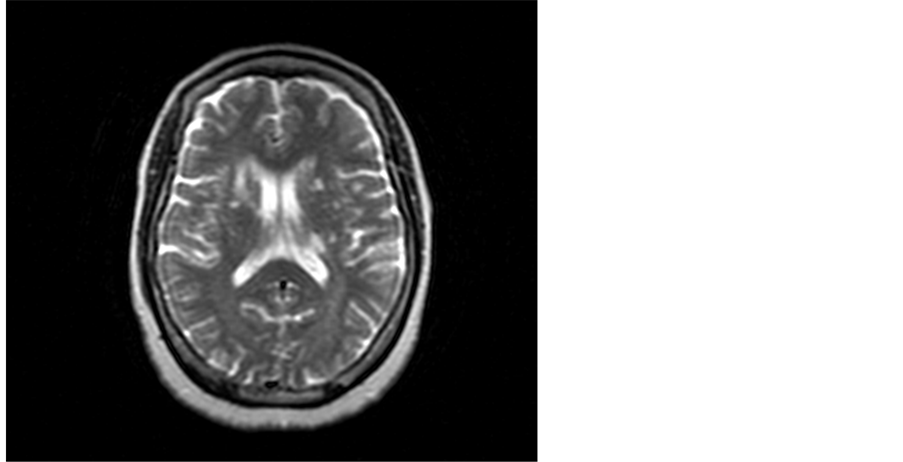

Demographic: With regards to gender, 60 patients (75%) were male and 20 patients (25%) were female. The mean group age was 42.4 years. Criteria and distribution of MRI brain lesions are described in Table 1, Figure 1, Figure 2 and Figure 3.

From the table we noticed that 50% of cases (24/48) had silent cerebral infarctions with periventricular white matter distribution, 33.3% (16/48) had infarcts in the basal ganglia and 16.66% had infarction in the thalamus.

Figure 3. A 61-year-old female A 61 bilateral basal ganglia foci of CSF signal and anterior limb of the right internal capsule and adjacent part of caudate nucleus lesion of high T2 signal.